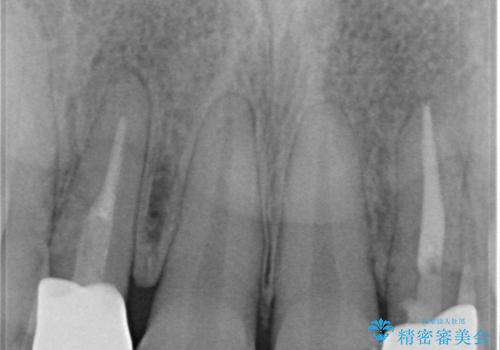

根管治療をしているため、歯の変色が認められます。

特に症状はなく、根管治療のやり直しは希望されなかったため、土台のやり替えから処置をしていくとととしました。